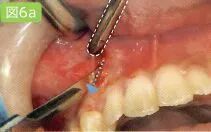

8 去除和刮治不良肉芽组织

拔牙窝最深处需要医生探头去看。所以口腔卫生士尽量要抓住医生不处于探头看的时候进行吸唾操作。有部分医生也可以独自完成治疗和吸唾的操作。

存在重度牙周病的牙齿,在其牙颈部和根尖部长有不良肉芽组织。这些不良肉芽组织会成为术后出血的诱因,因此要事先用刮匙将其彻底清除干净。

吸唾器的操作目的

1,确认拔牙窝处是否残留了部分破损的牙冠、牙根以及碎屑。

2,确认邻牙上是否附着牙结石,是否有龋蚀。

3,刮治过程中,保证不良肉芽组织周围术野。

吸引拔牙窝。不过,拔智齿时,可能会暴露下牙槽神经。向医生确认下牙槽管是否有暴露的可能性之后,再吸引拔牙窝底部。对口腔卫生士而言必须依靠经验掌握插入吸唾器的深度。

此外,进行刮治时使用吸唾器吸引刮匙操作的区域。

刮治后,为了确认邻牙是否有牙结石附着和龋,可以使用吸唾器吸引邻在牙侧面。医生和其助手的术野是不同的。特别是较小拔牙窝,根据角度的不同,可能会导致主治医生观察时视线被阻碍。口腔卫生士在确认了是否有不良肉芽组织残留和破损牙根之后,要将自己所处角度看到的情况传达给医生。

刮治时吸引手刮匙的操作部位